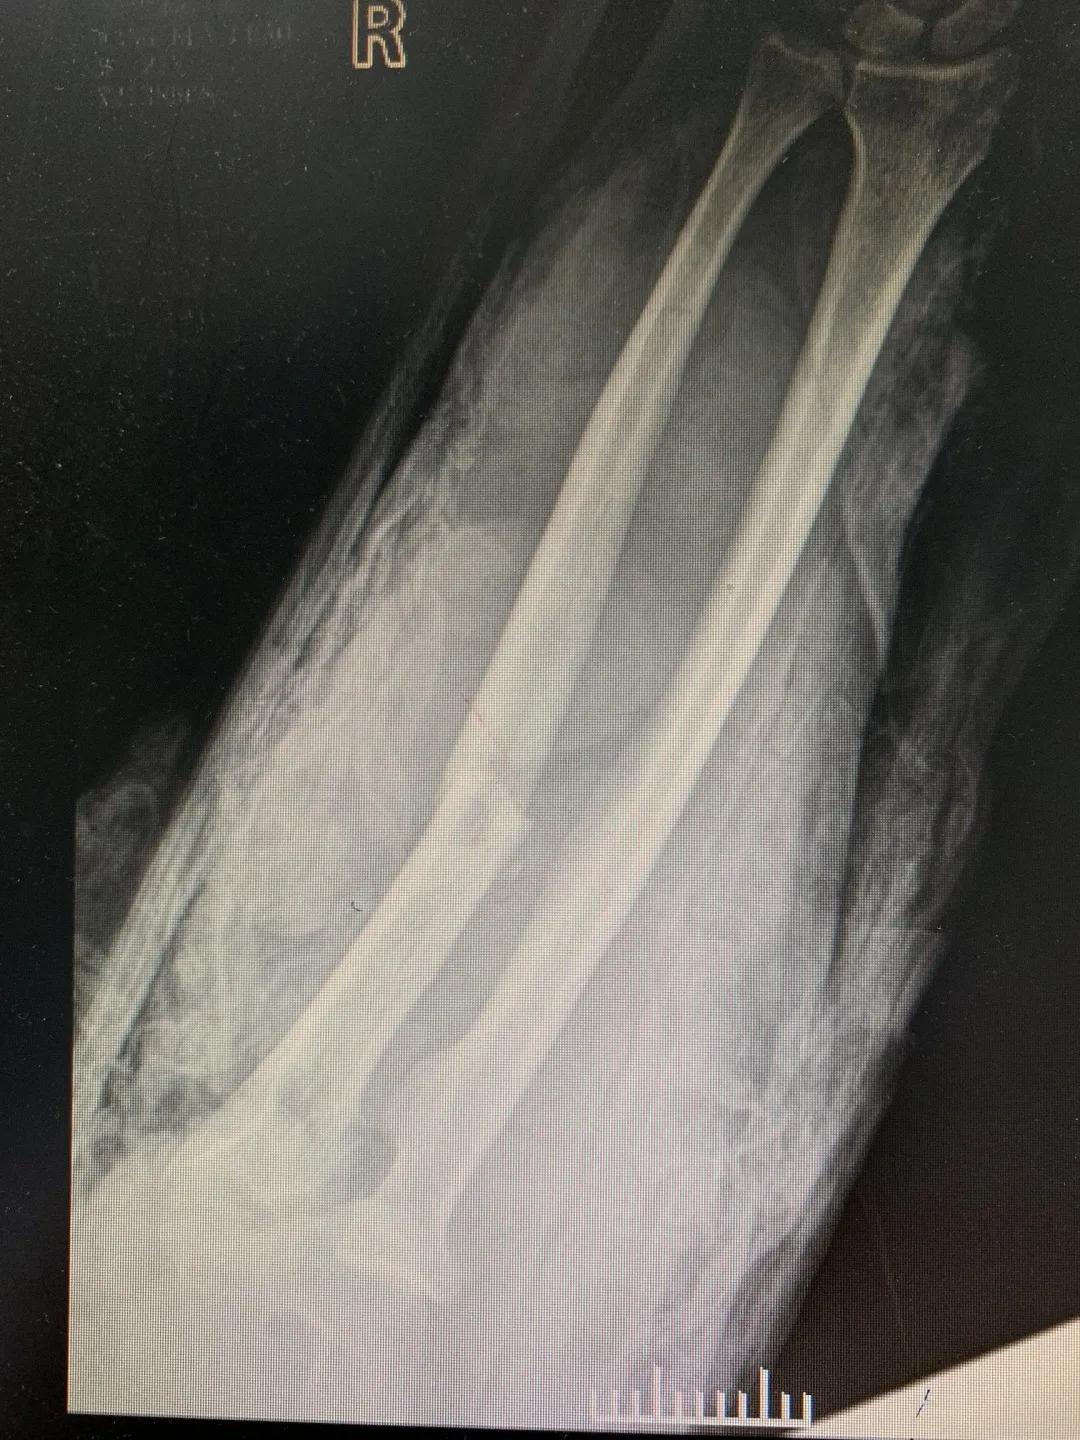

“正常的肢体都有皮肤保护着,如果没有皮肤,我们的肌肉、血管、神经、骨骼露在外面,都会发生坏死。”苑芳昌介绍,伤者的情况非常复杂,伴有多发骨折、肱骨骨折、骨关节的多发错位,还有腕部的骨折,更有血管、神经损伤。不仅如此,伤者右臂在机器里面受到绞伤,肌肉也已经大面积挫伤,各种复杂情形交织在一起甚至让手术“无从下手”。

清创、止血、接骨、将粉碎的骨块一块块拼接完整,同时给予VSD敷料负压引流。经过三次清创清除后,明确了坏死的皮肤等组织,创面好转,肉芽组织良好……